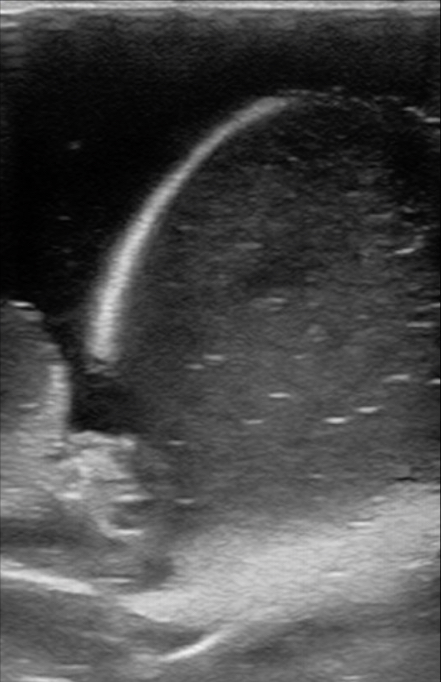

Figure 12. A model with normal testicle, epididymis in view, and a hydrocele.